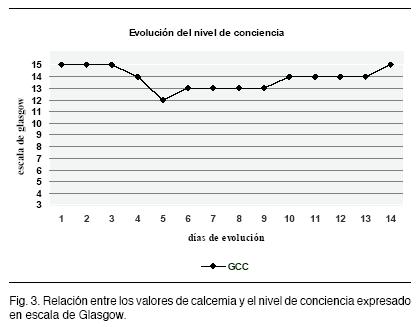

A las 72 hs., coincidiendo con el aumento de la cifra de calcemia, instaló depresión de conciencia, en apirexia y sin elementos de hipertensión endocraneana ni focalidad neurológica, presentando al examen un Glasgow 12 (Figuras 3 y 4). Se plantea su etiología metabólica (hipercalcemia, deshidratación) y se descartan causas infecciosas o estructurales (tomografía de cráneo normal y punción lumbar con citoquímico normal y cultivo estéril).

En el caso clínico analizado observamos que el nivel de calcemia se correlaciona con el deterioro del nivel de conciencia. Coincidiendo con la literatura revisada.